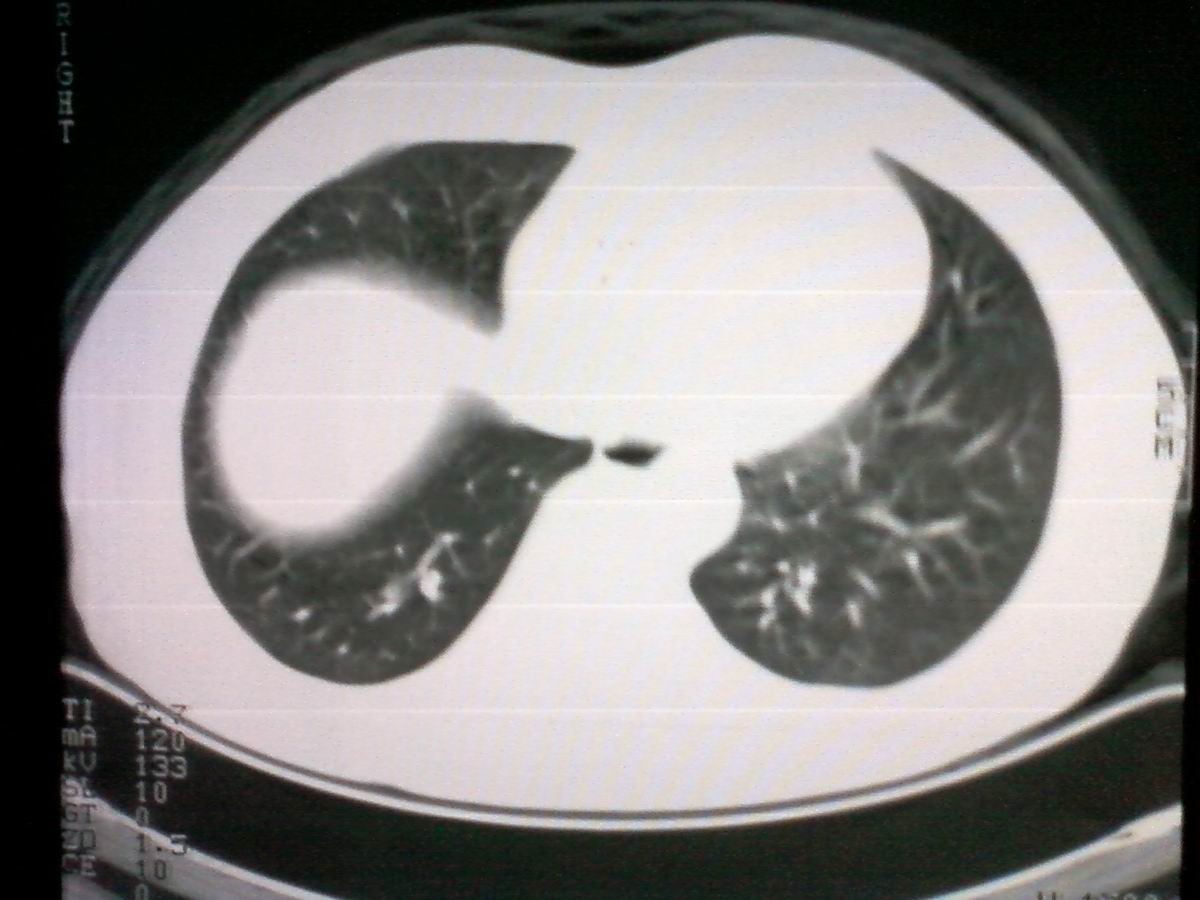

标题: CT25801:患者男性,65岁,临床提示双肺可闻及广泛罗音,看 [打印本页]

标题: CT25801:患者男性,65岁,临床提示双肺可闻及广泛罗音,看

仅见肺纹理影增重 纵膈淋巴结钙化